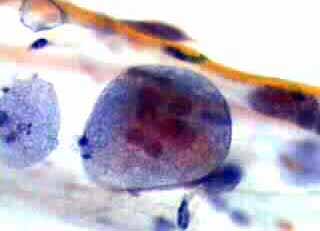

Η εμφάνιση γιγαντιοκυττάρων κυρίως της επί πολλής και της διαμέσου στιβάδος με χαρακτηριστικές εκφυλιστικές αλλοιώσεις του κυτταροπλάσματος και του πυρήνα, στο κυτταρολογικό επίχρισμα κατά Papanicolaou, απαντάται στον έρπητα του τραχήλου της μήτρας..

Εικόνες γιγνατιοκυττάρων με πολλαπλούς πυρήνες συναντούμε επίσης και σε περιπτώσεις εκσεσημασμένης ατροφίας του κολπικού επιθηλιου. Εδώ όμως δεν πρόκειται για γνήσια γιγαντιοκυττάρωση, αλλά για έκφραση εκφυλιστικής αλλοίωσης, που συνίσταται στην σύντηξη περισσοτέρων κυττάρων.

Επίσης, σποραδική εμφάνιση γιγαντιοκυττάρων διαπιστώνουμε και σε επιχρίσματα με εικόνα καλής οιστρογονικής επίδρασης, με πυκνωτικούς πυρήνες, χωρίς άλλη μορφολογική διαταραχή. Την γιγαντιοκυτταρωση αυτού του τύπου θα την συνατήσουμε σε επιχρίσματα γύρω στο μεσοκύκλειο, ή σε επιχρίσματα κλιμακτηριακών γυναικών, με υψηλό ποσοστό οξεοφιλίας. Η εμφάνιση τους δεν εντάσσεται σε καποια ειδική αιτία. Πιθανώς να είναι έκφραση καποιας ιογενούς συμμετοχής.